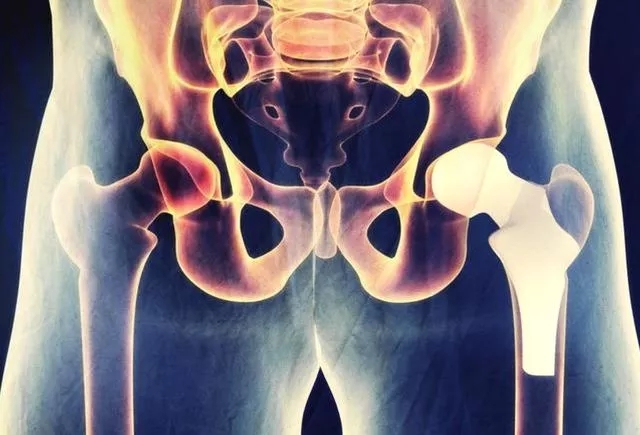

股骨头坏死,别慌!

因为股骨头坏死的部位在髋关节,是人体较大、较重要的承重关节,得了股骨头坏死后会出现髋关节疼痛、行走障碍、走路跛行。所以很多人就觉得股骨头坏死非常可怕,导致有病乱投医。

其实股骨头坏死本身并不可怕,得了股骨头坏死也不要觉得自己就是一个残疾人。因为股骨头坏死经过恰当的治疗,是完全可以获得良好治疗效果的,是骨科病里治疗效果比较好的典范。